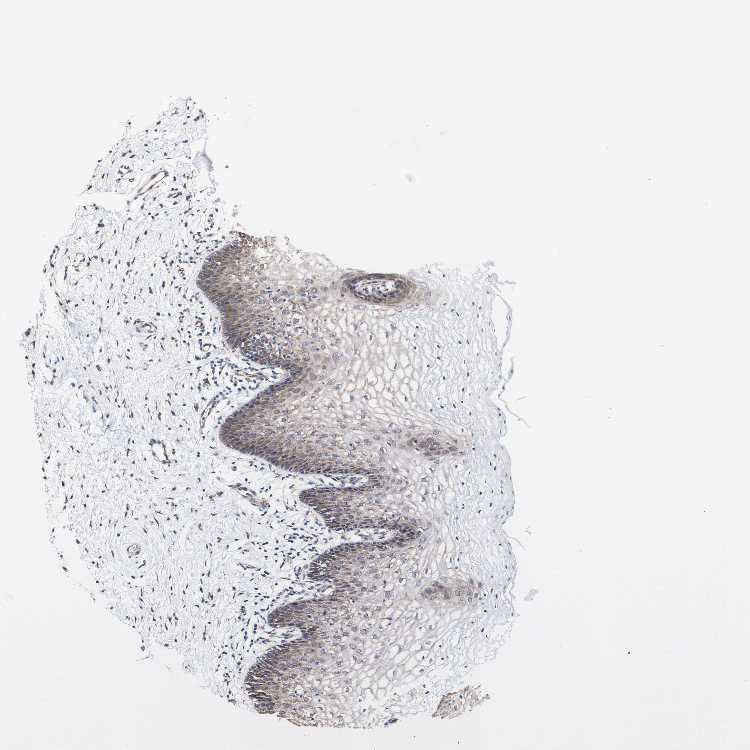

TISSUE PRIMARY DATA VAGINA Show tissue menu

VAGINA - Antibody stainingi

Antibody staining in the annotated cell types in the current human tissue is reported as not detected, low, medium, or high, based on conventional immunohistochemistry profiling in selected tissues. This score is based on the combination of the staining intensity and fraction of stained cells.

Each image is clickable and will lead to virtual microscopy that enables deeper exploration of all samples and also displays staining intensity scores, fraction scores and subcellular localization as well as patient and tissue information for each sample.

Antibody HPA010773

Squamous epithelial cells Medium